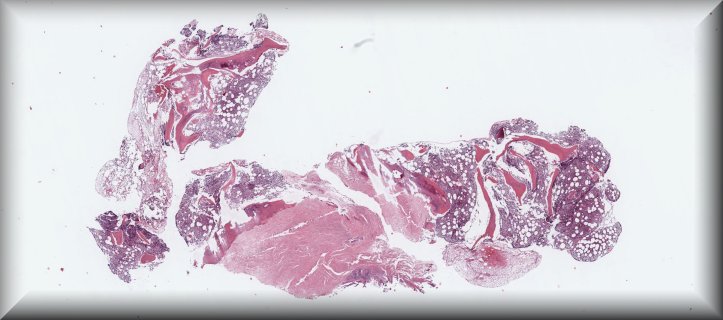

Caso 5.- Francisco Javier Aguilar López; Laura Heredia Oliva; Ludy Marcela Cervera Vergara; Francisco Jesús Quintero Rascón.

Hospital General Universitario de Elche.

Pancitopenia a estudio en el contexto desíndrome constitucional de aproximadamente 1 año de evolución, sin fiebre objetivada.Vida y trabajo en medio rural; contacto con tres perros.Viajes previos a Cuba y Bolivia. Linfocitopenia crónica referida.TAC: gran esplenomegalia con lesionesnodulares esplénicas; hepatomegalia; nódulos pulmonares subpleurales.